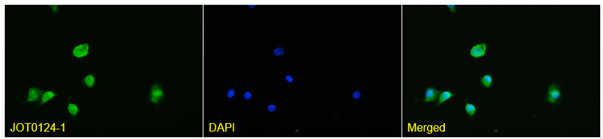

Anti-SARS-CoV-2 spike RBD VHH antibody

Product code: JOT0007-1